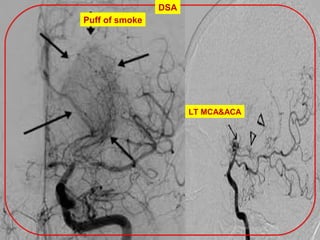

Puff of smoke

DSA

LT MCA&ACA

hazy cloud

Stenosis

No ACA

moyamoya.